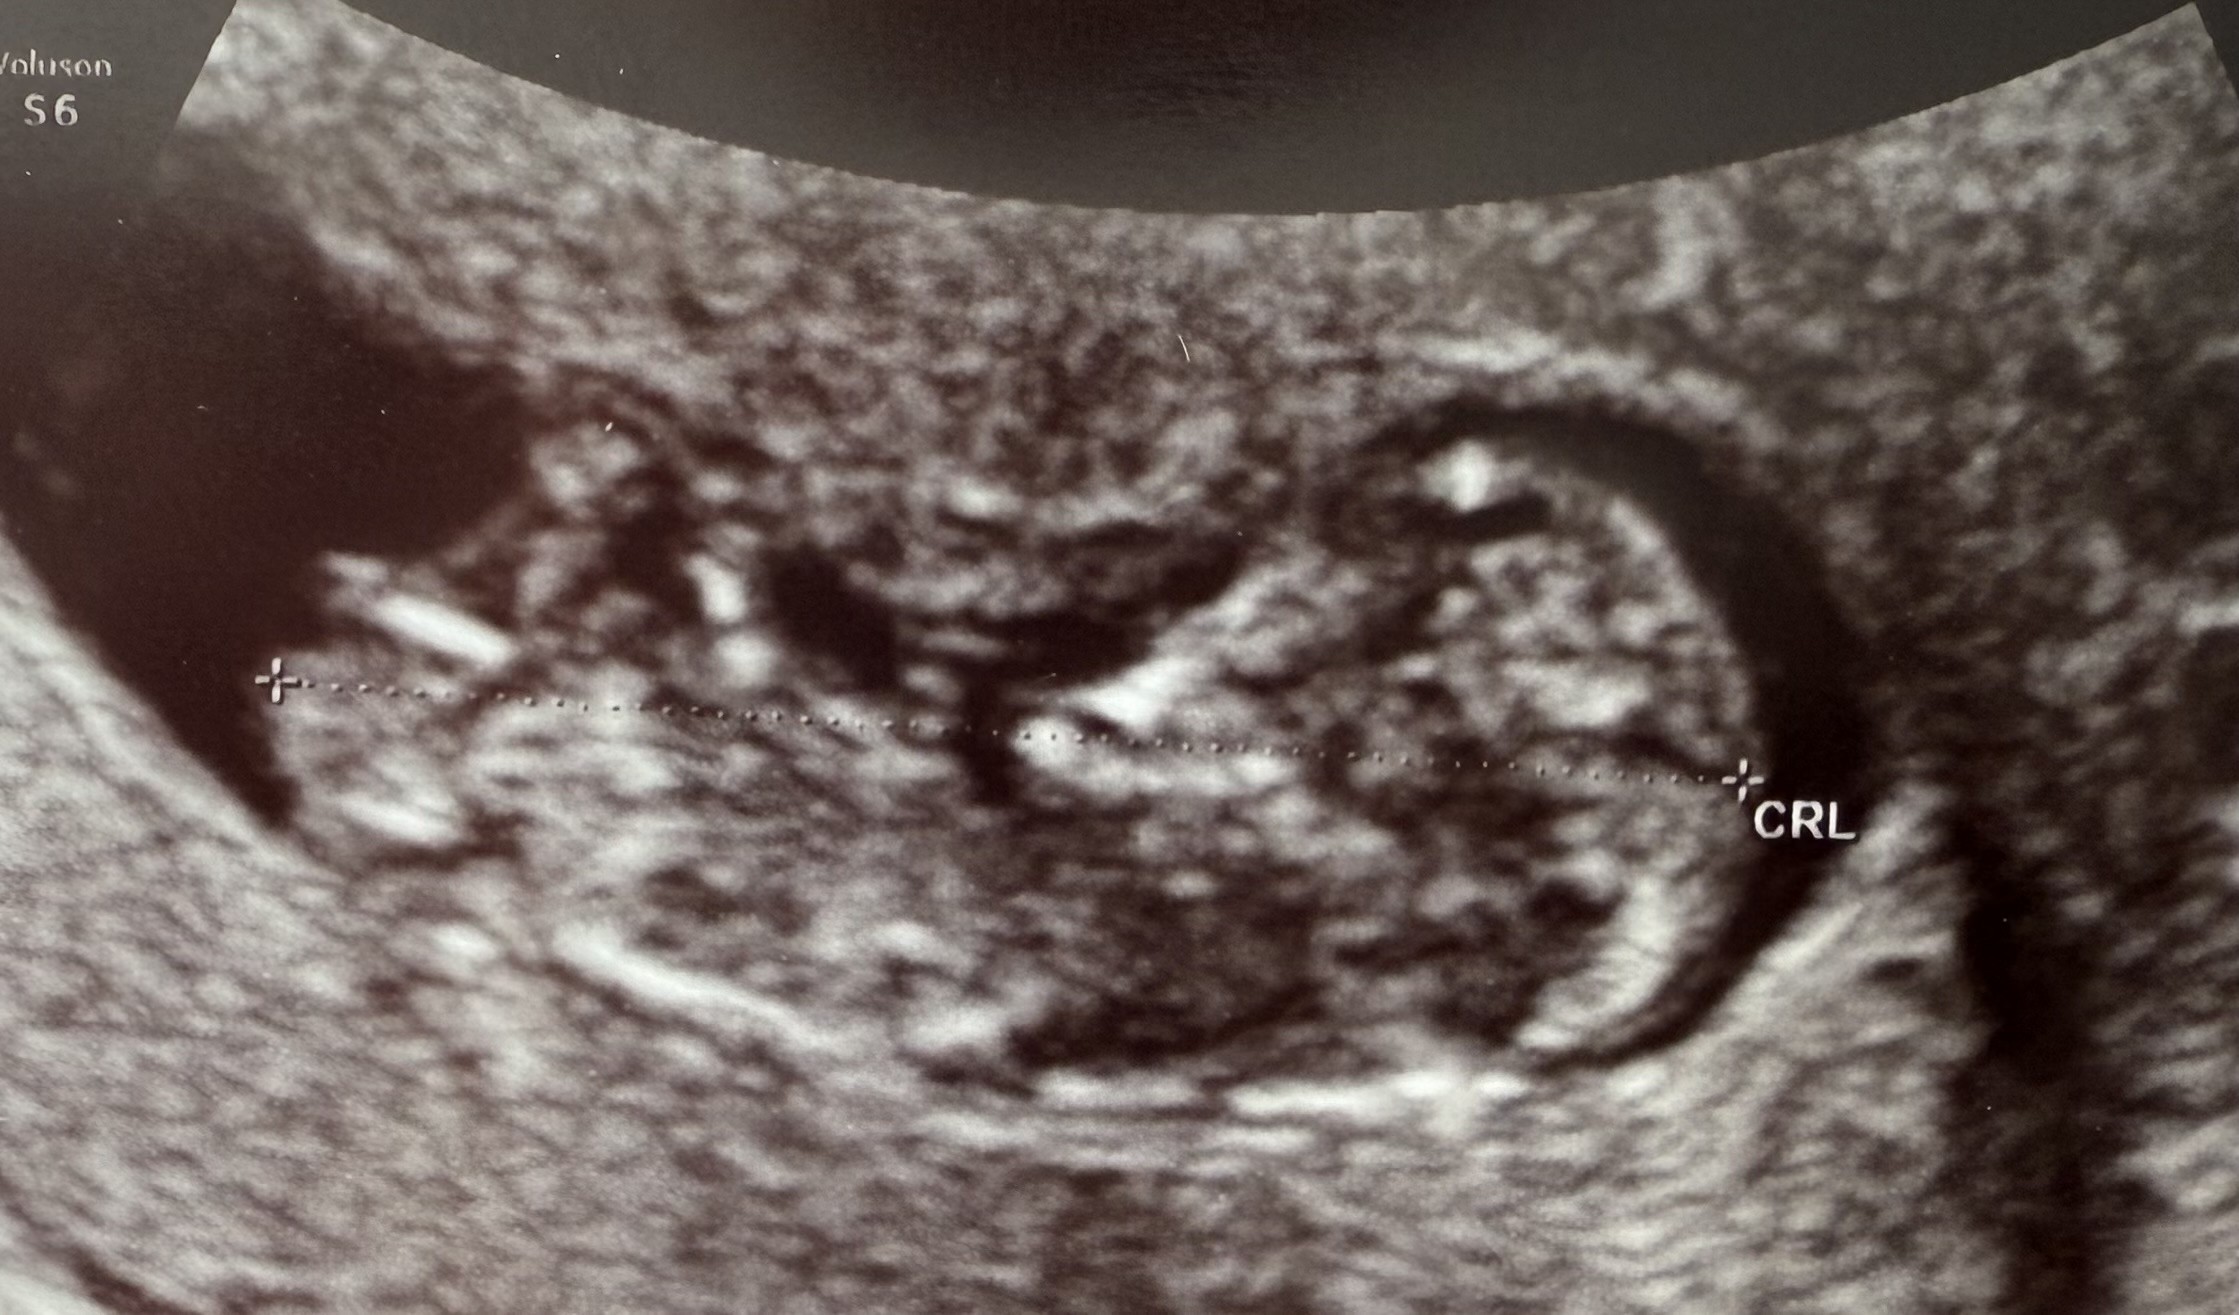

To jest nasze 4,8 cm dziecię i świecący wyrostek płciowy 😜

Załączniki

• IMG_8719.jpeg

IMG_8719.jpeg

471,4 KB · Wyświetleń: 81